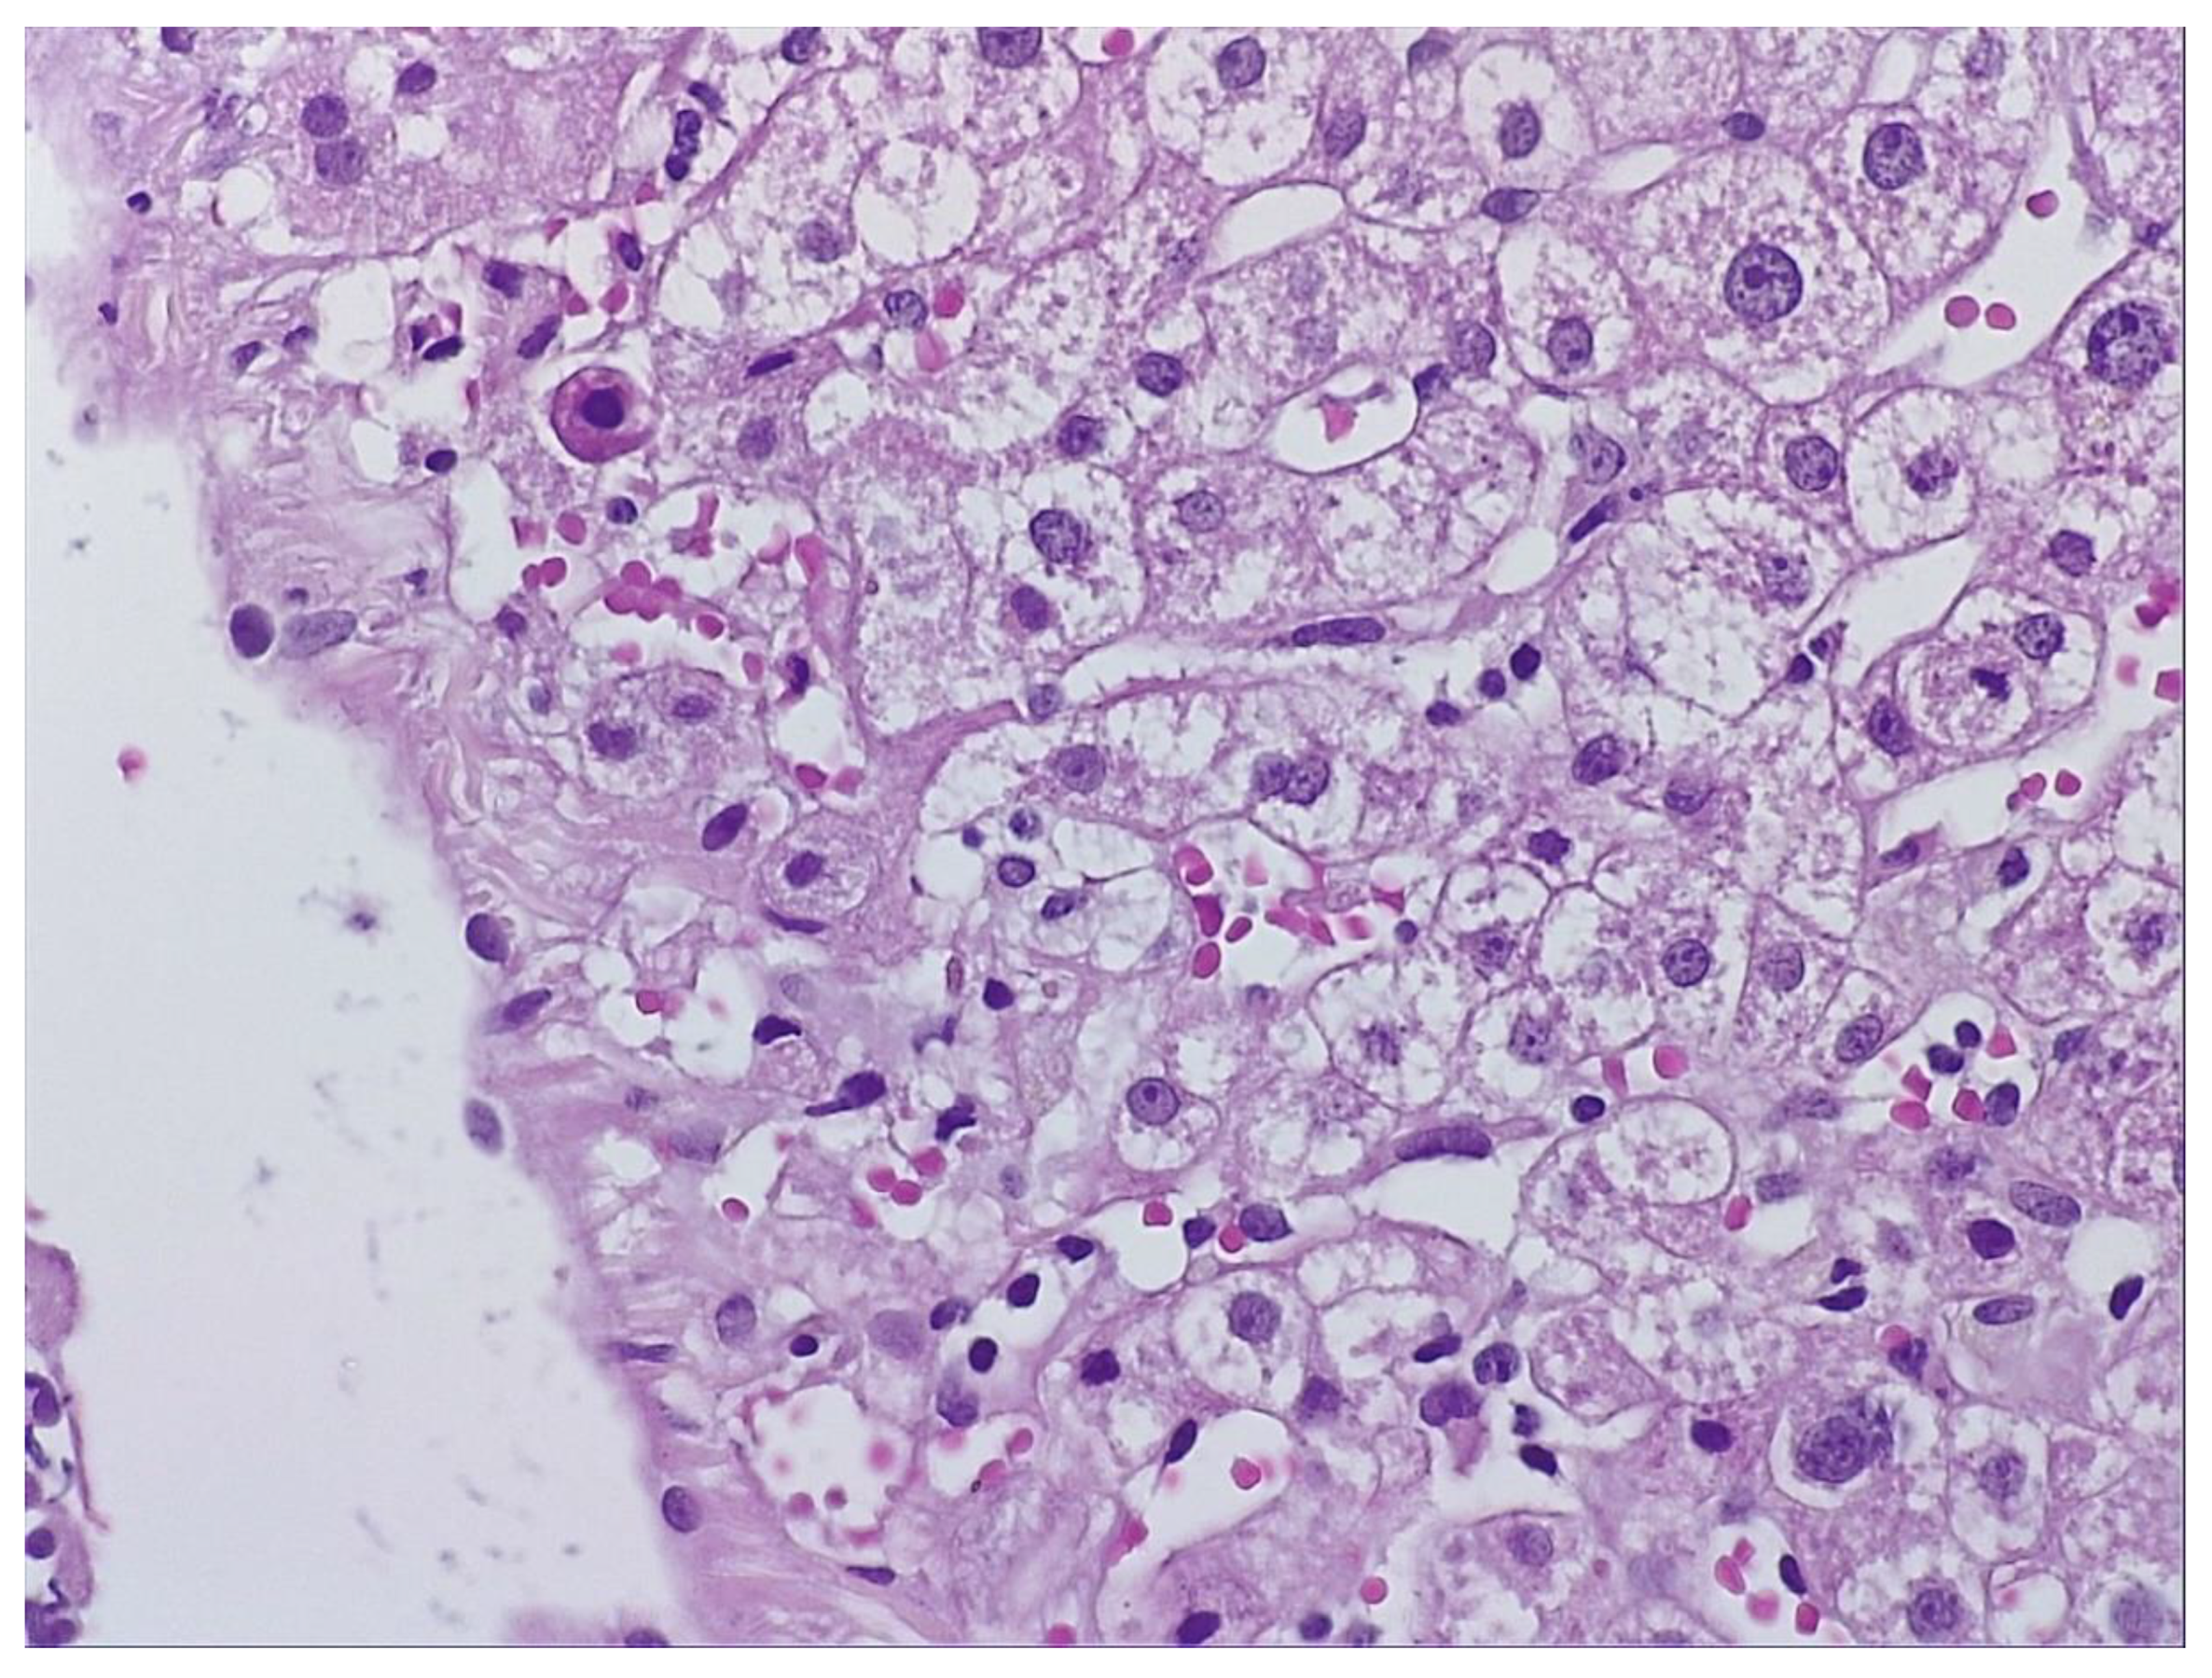

During hospitalization, the patient received hepatoprotective therapy consisting of silymarin, essential phospholipids and amino-acids, and L-arginine, alongside solutions for metabolic support and hydro-electrolytic rebalancing. Initial favorable clinical evolution allowed discharge; however, the patient re-presented to the hospital a few days post-discharge due to symptom recurrence. To establish the etiopathogenesis of the hepatocitolytic syndrome, a liver biopsy was performed. Histology described mild-to-moderate portal tract expansion with lymphoplasmocytic inflammation, preserved portal triad without pathological fibrosis and without interface hepatitis. Numerous apoptotic hepatocytes and focal confluent necrosis were noted, but without bridging necrosis. No histological signs of cholestasis or steatosis were identified. The overall picture was that of moderate-to-severe portal and lobular hepatitis without specific features; therefore, a possible herb-induced liver injury (HILI) could not be excluded. (Figure 1 and Figure 2.)

„The biopsy core measures 14 mm in length and, on histological sections, is thin but adequate, showing preserved lobular architecture of the hepatic parenchyma. Two portal tracts and seven centrilobular veins are identified. The portal tracts are mildly to moderately expanded with lymphoplasmacytic inflammatory infiltrate; the portal triad is preserved, without pathological fibrosis and without interface hepatitis. Within the lobules, there is hepatocellular ballooning (dystrophic change), numerous apoptotic hepatocytes, focal and confluent necrosis without bridging necrosis; frequent typical mitoses and regenerative hepatocellular rosettes are also noted. There is no histological evidence of cholestasis or pathological steatosis.” Histopathological interpretation corresponding to Figure 1 and Figure 2.

Figure 1. Biopsy fragment – H&E staining.